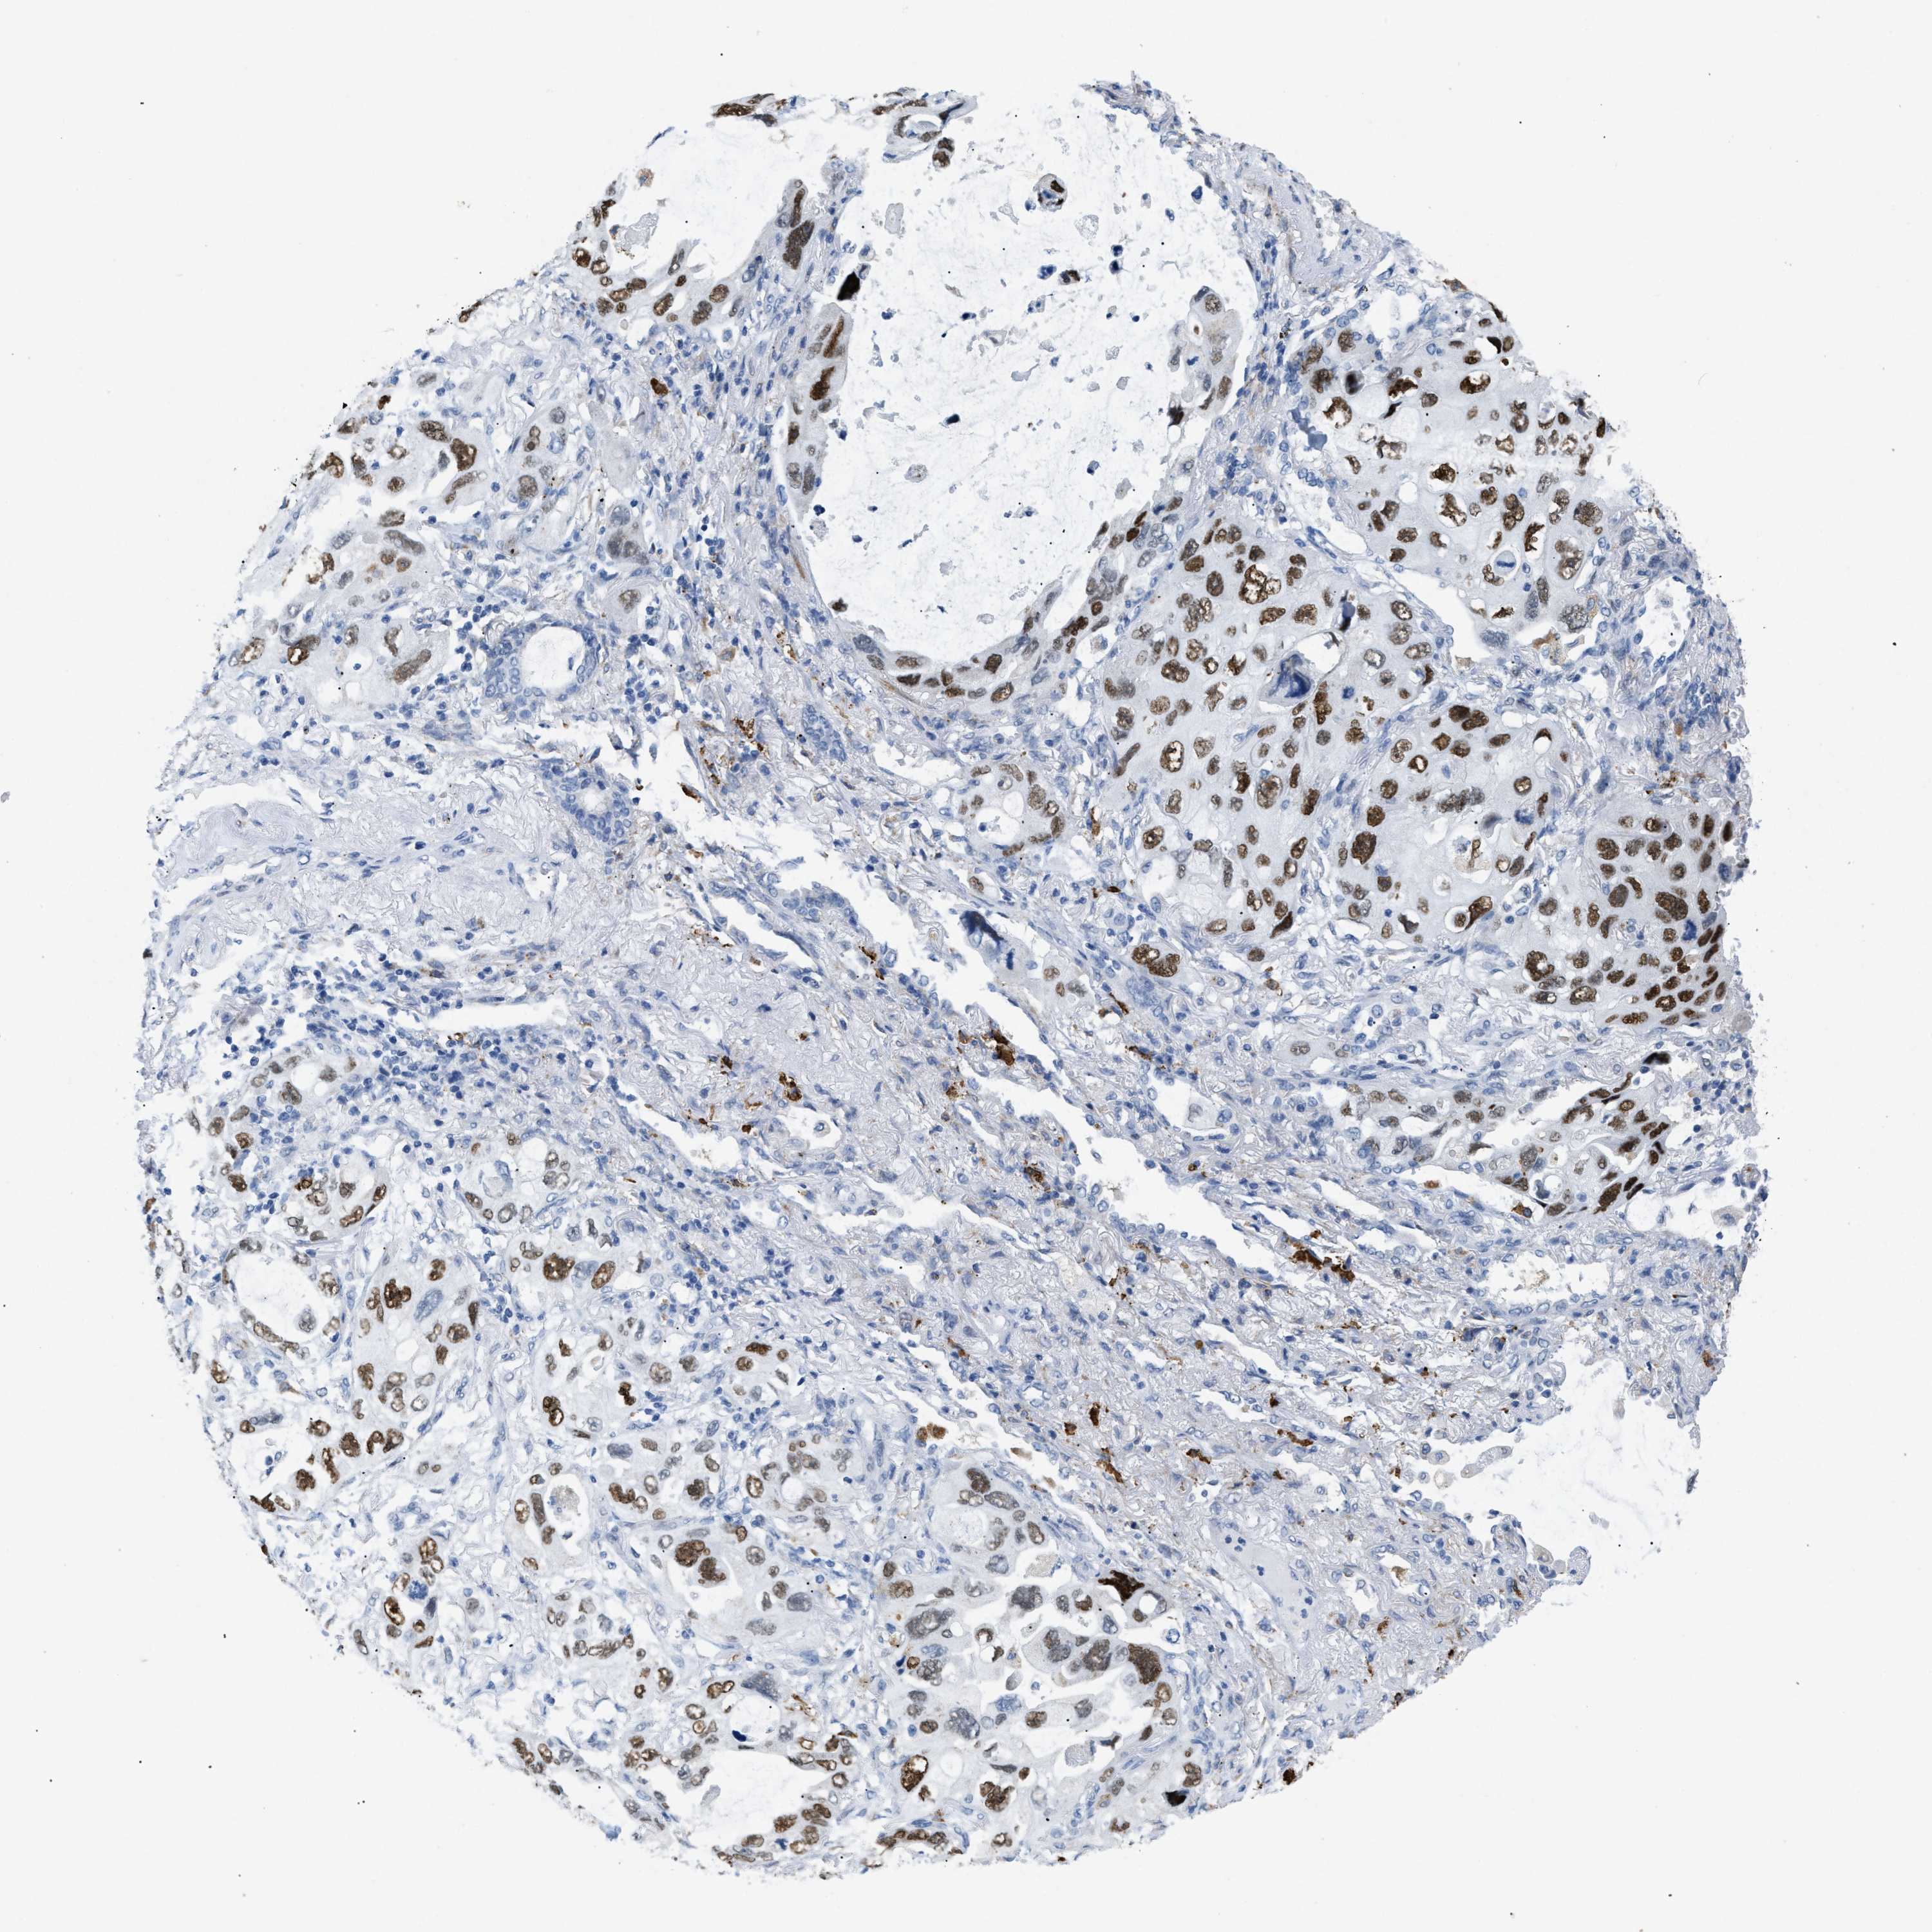

CANCER LUNG CANCER Show tissue menu

LUAD TCGA LUAD VALIDATION LUSC TCGA LUSC VALIDATION PROTEIN LUAD CPTAC PROTEIN LUSC CPTAC PROTEIN EXPRESSION